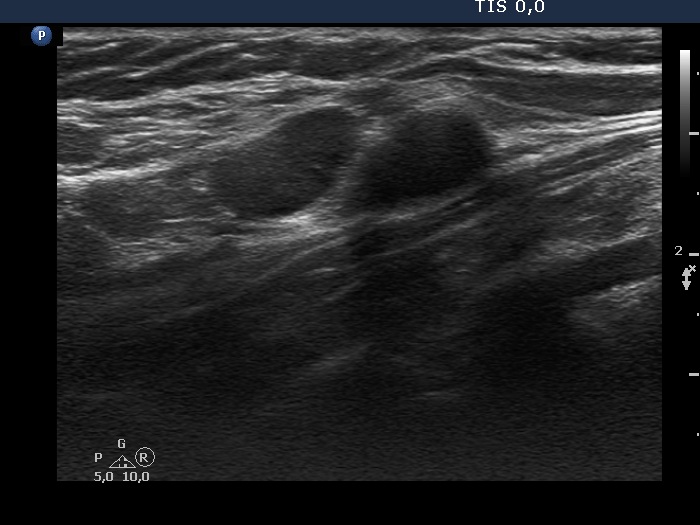

First examination (first, third and fifth rows of images):

Ultrasonography. The thyroid was echonormal and contained multiple inhomogeneous, partly blurred hypoechogenic and moderately hypoechogenic discrete lesions. Multiple lymph nodes were found on both sides of the neck.